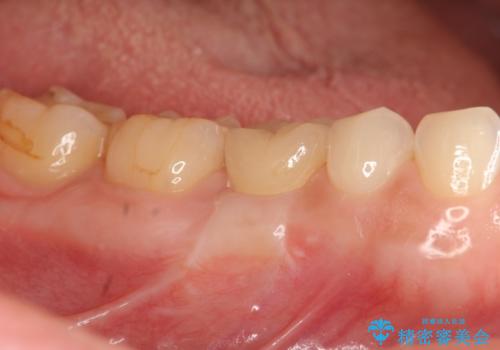

[20代男性] インプラント 失った歯の治療

![[20代男性] インプラント 失った歯の治療の症例 治療後](https://seimitsushinbi.jp/wp/wp-content/uploads/2019/11/IMG_9922-1-500x350.jpg?v=1574736466)